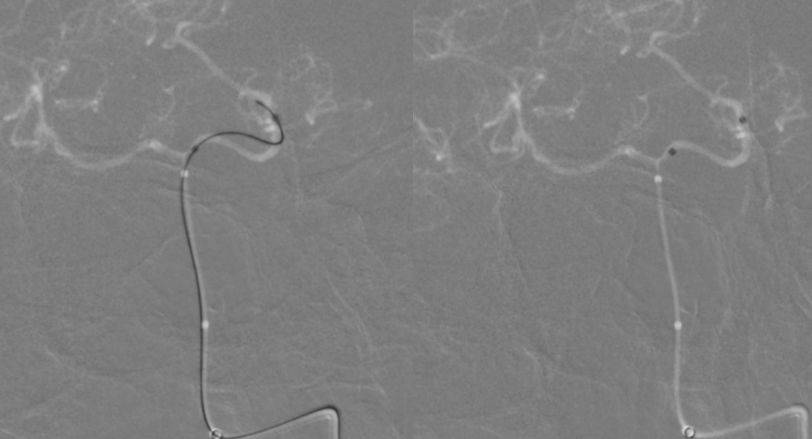

2、调整至合适的工作角度后,撤出5F中间导管,将5F Navien 通过6F长鞘置入左侧V3段。路图引导下由2 m Synchro-14微导丝将T-track支架微导管超选进左侧大脑后动脉P2段(图9)。

图9